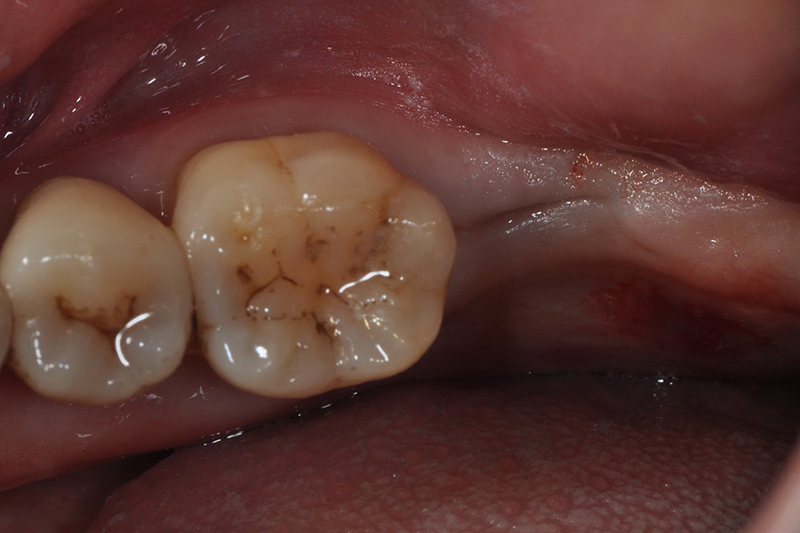

缺牙多顆

案例一

術前